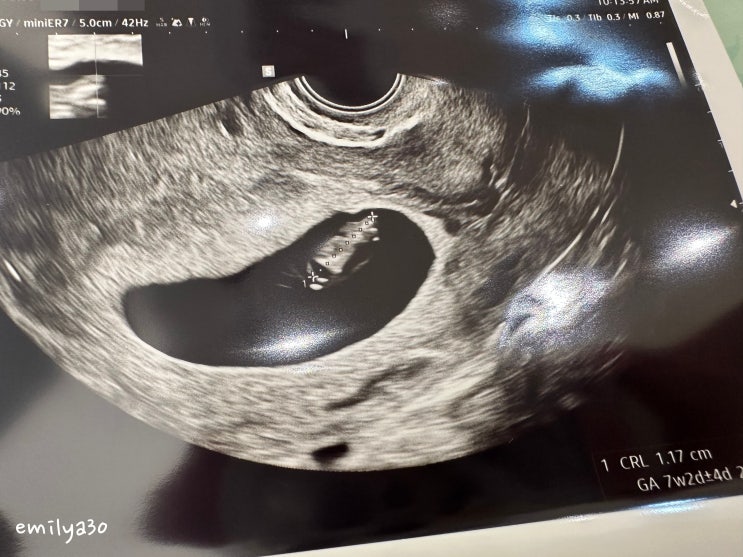

임신 7주차 / 걱정맘은 서브 병원에 간다...

임신 7주차, 걱정 맘은 서브 병원에 간다... 봄이 7주차 진입. 하루, 하루 시간이 정말 더디게 간다. 임신 ...